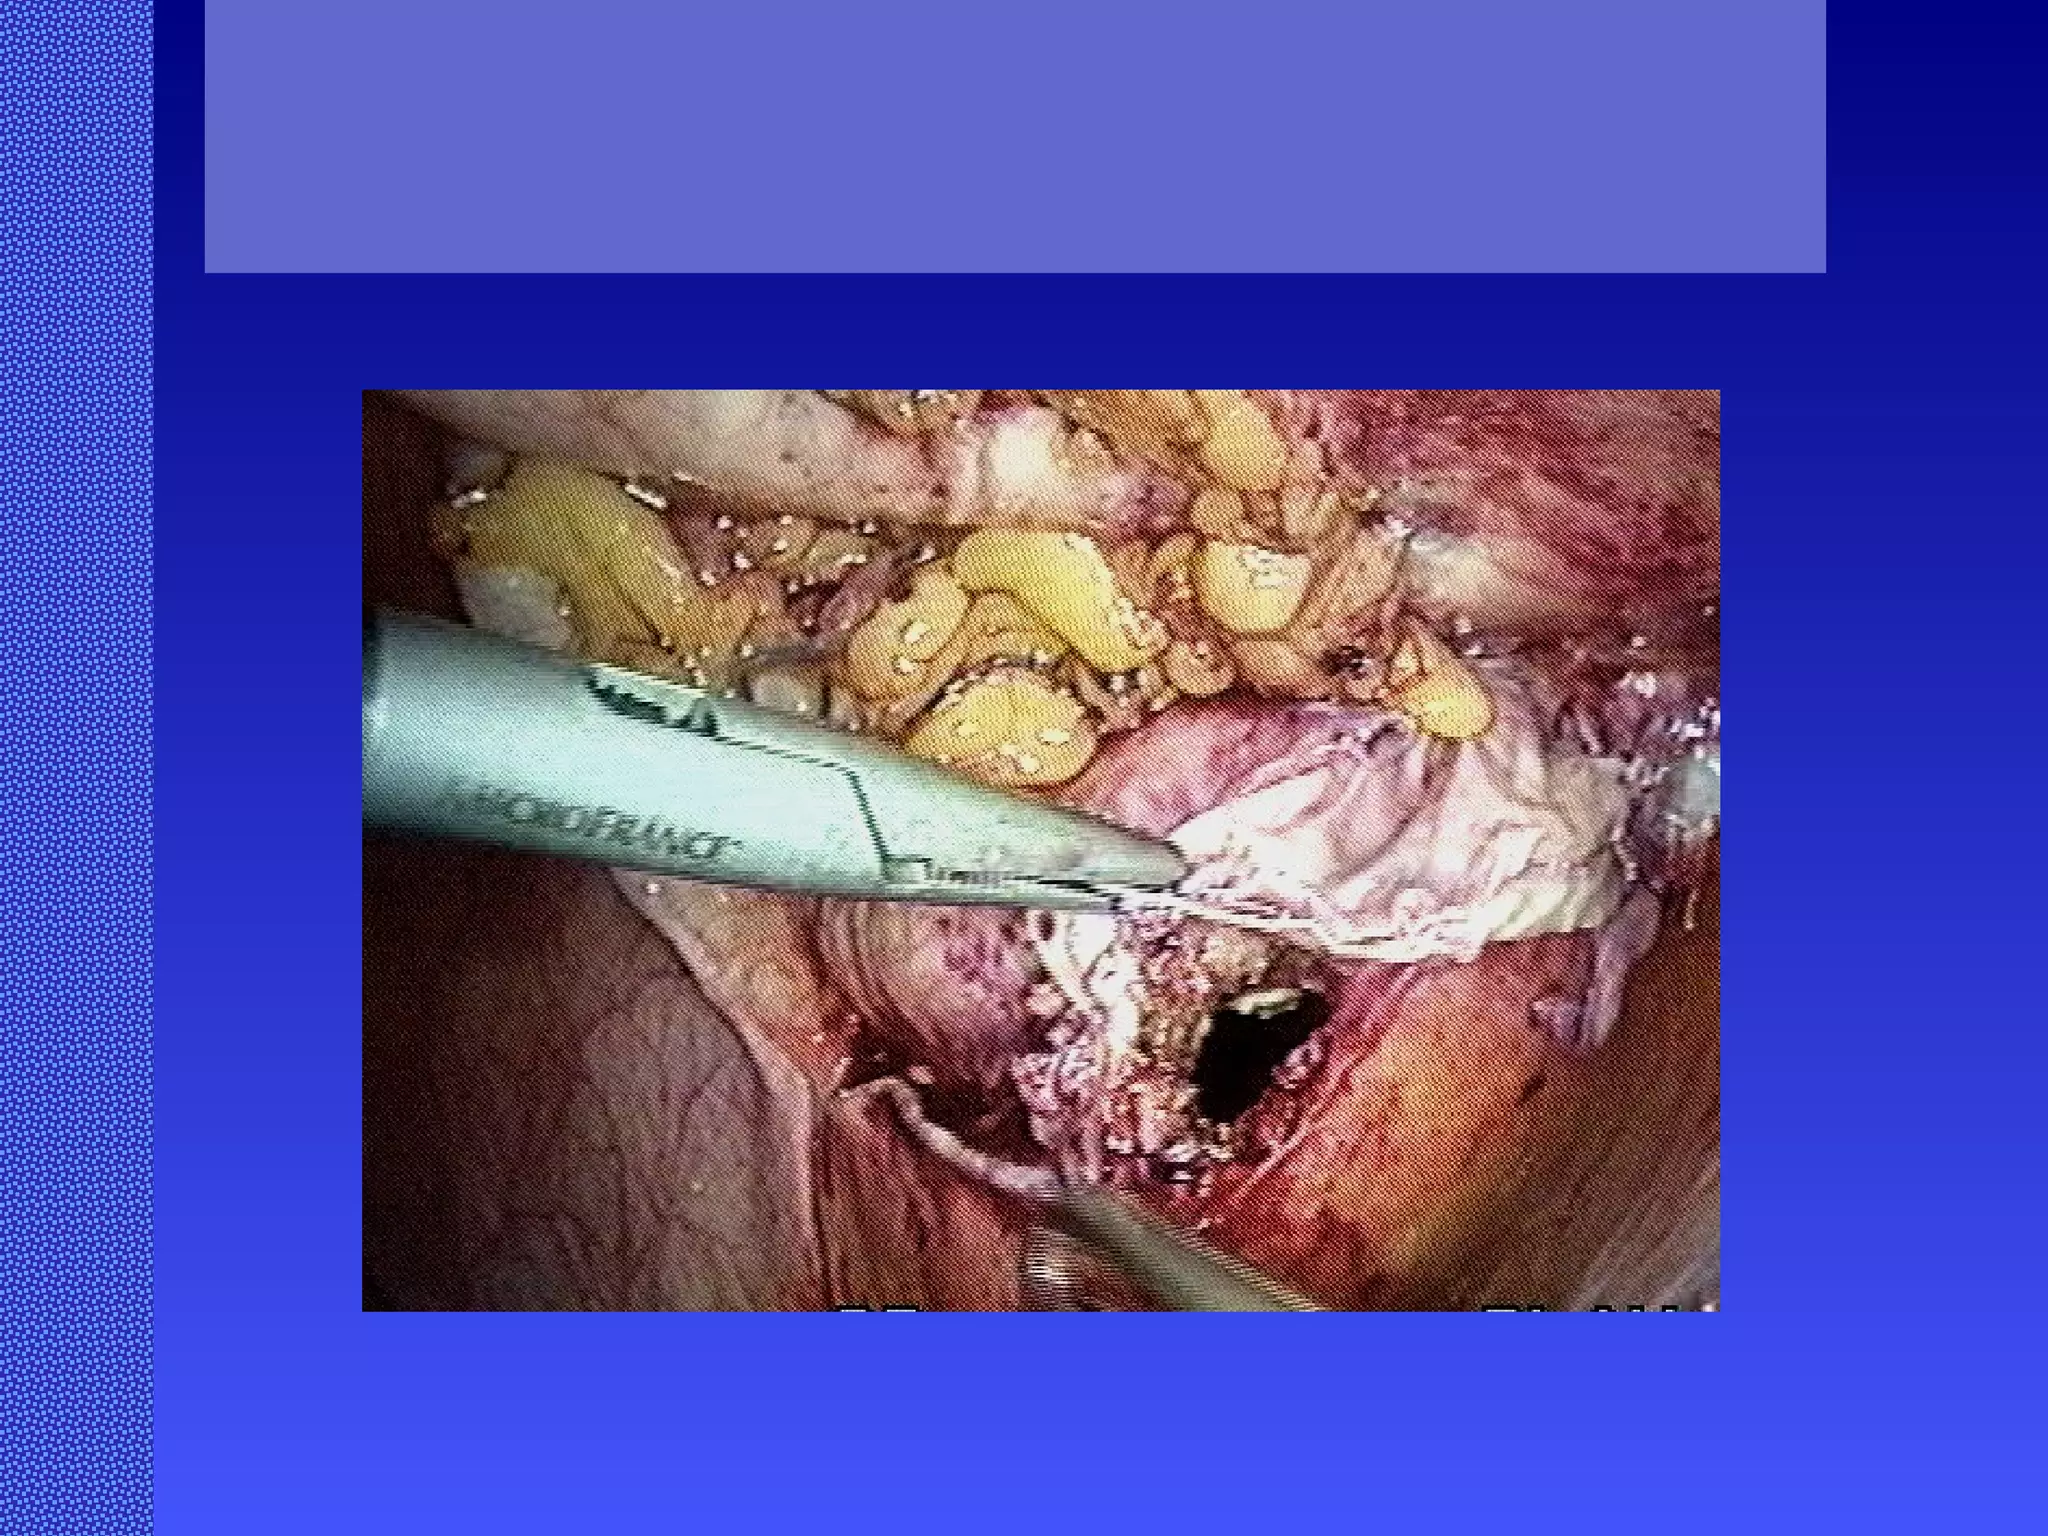

Abdominal Wall Reconstruction: Lessons Learned From 200 “Components Separation” Procedures. Ko, J, MD; Wang, E, PhD; Salvay, D, MS; Paul. B, BA; Dumanian, G, MD  ArchSurg /vol 144 (No. 11), Nov 2009  www.archsurg.com Figure 1. Modified “components separation” technique using bilateral transverse subcostal incisions to access the external oblique muscle and fascia . A, Using a narrow Deaver retractor and a Bovie cautery with and extender, the external oblique muscle and fascia are divided superiorly (above the rib cage) and inferiorly. B, At the caudal aspect of the midline incision, the cut edge of the external oblique muscle and fascia is delivered using manual traction for complete release.

Abdominal Wall Reconstruction: Lessons Learned From 200 “Components Separation” Procedures. Ko, J, MD; Wang, E, PhD; Salvay, D, MS; Paul. B, BA; Dumanian, G, MD  ArchSurg /vol 144 (No. 11), Nov 2009  www.archsurg.com •   Senior author Gregory Dumanian adapted his surgical technique to perform the external oblique releases through  bilateral transverse subcostal incisions to avoid wide undermining, an evolution of the technique of “periumbilical perforator preservation .” Releases take only 15-20 minutes to perform and avoid the setup of endoscopic equipment.